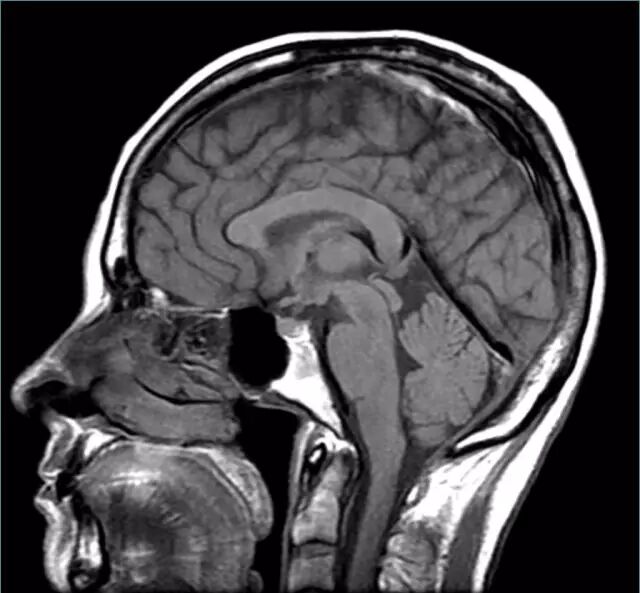

让我们使用半球横截面看看大脑的主要部分。因此,这是你脑袋里大脑的样子:

现在,让我们把大脑取出来,并删除左半球,这让我们能看清楚内部。